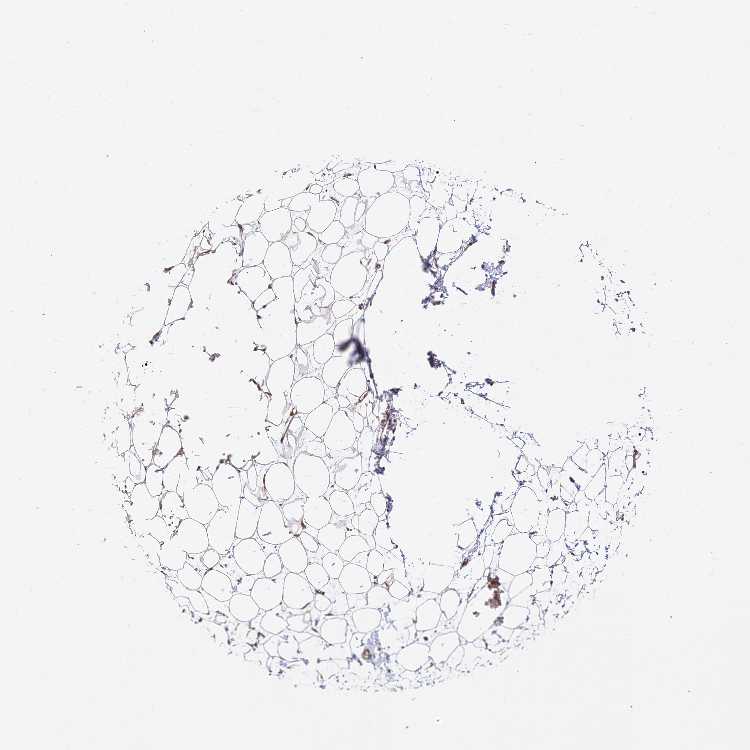

BREAST - Antibody stainingi

Antibody staining in the annotated cell types in the current human tissue is reported as not detected, low, medium, or high, based on conventional immunohistochemistry profiling in selected tissues. This score is based on the combination of the staining intensity and fraction of stained cells.

Each image is clickable and will lead to virtual microscopy that enables deeper exploration of all samples and also displays staining intensity scores, fraction scores and subcellular localization as well as patient and tissue information for each sample.

Antibody HPA042996Antibody HPA045576Antibody HPA049949

Adipocytes LowNot detectedNot detected

Glandular cells MediumHighMedium

Myoepithelial cells MediumLowMedium